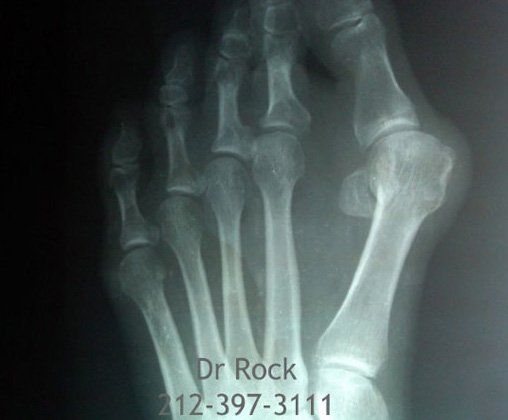

Take a look at our x-ray pictures of our recent footwork and see how your feet can benefit.

for more X-ray photos.